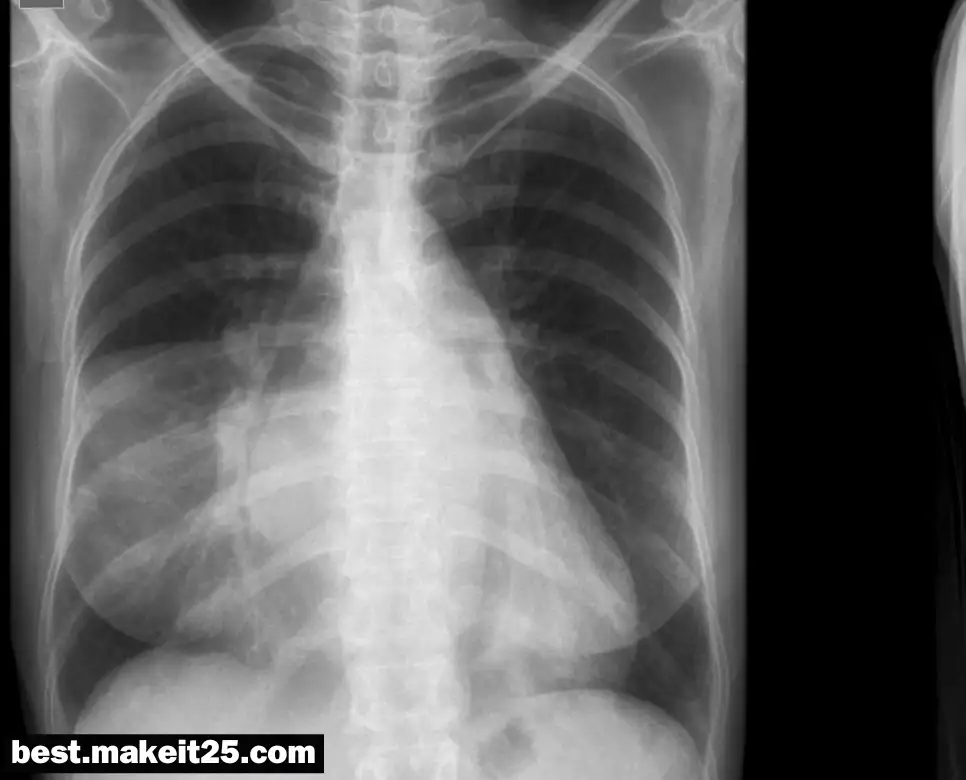

LLL은 의학 용어로 Left Lower Lobe를 의미하며, 한국어로는 좌하엽이라고 합니다. 이는 흉부의 해부학적 구조 중 하나로, 왼쪽 폐의 아래쪽 부분을 가리킵니다. LLL은 폐의 기능과 관련된 다양한 질환에서 중요한 역할을 하며, 특히 호흡기 질환의 진단과 치료에 있어서 중요한 부위입니다.

LLL의 해부학적 위치와 기능

LLL은 왼쪽 폐의 세 부분 중 하나로, 다음과 같은 특징을 가집니다:

- 위치: 왼쪽 폐의 아래쪽 부분에 위치하며, Oblique Fissure에 의해 좌상엽(LUL)과 구분됩니다.

- 기능: 호흡 과정에서 공기 교환을 담당하며, 산소를 혈액으로 전달하고 이산화탄소를 배출하는 역할을 합니다.

LLL 관련 질환

LLL은 다음과 같은 질환과 관련이 있습니다:

- 폐렴 (Pneumonia): LLL에 감염이 발생하여 염증이 생기는 질환입니다.

- 폐결핵 (Tuberculosis): 결핵균에 의한 감염으로 LLL에 영향을 줄 수 있습니다.

- 폐암 (Lung Cancer): LLL에 암세포가 발생하는 경우로, 진단과 치료가 필요합니다.

LLL의 진단과 치료

LLL의 질환 진단에는 다음과 같은 방법이 사용됩니다:

- X-ray: 흉부 X-ray를 통해 LLL의 이상 유무를 확인할 수 있습니다.

- CT 스캔: 좀 더 상세한 이미지를 통해 LLL의 상태를 평가합니다.

- 기관지경 검사 (Bronchoscopy): LLL 내부를 직접 관찰하여 이상 유무를 확인합니다.

치료는 질환의 종류와 정도에 따라 다르며, 약물 치료, 수술, 방사선 치료 등이 포함될 수 있습니다.

LLL은 폐의 중요한 부분으로, 호흡기 질환의 진단과 치료에 있어 핵심적인 역할을 합니다. 의료진은 LLL의 상태를 평가하여 환자의 건강 상태를 정확히 파악하고, 적절한 치료 계획을 세울 수 있습니다. 환자는 LLL에 대한 이해를 통해 자신의 건강 상태를 더 잘 관리할 수 있게 됩니다.